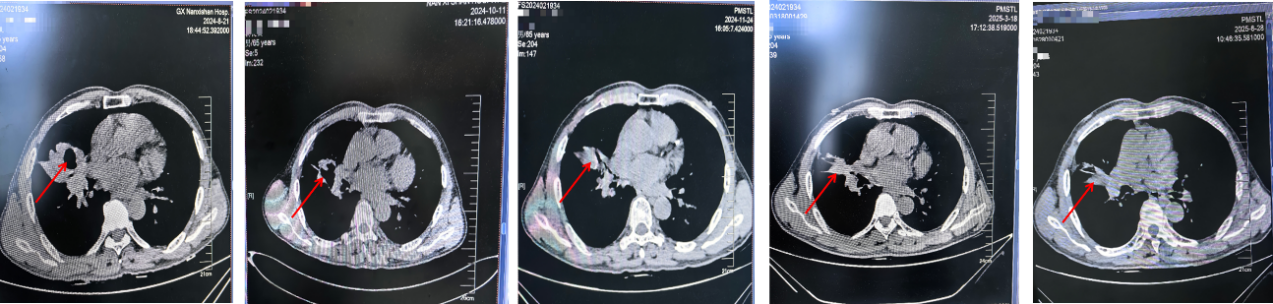

胸部增强CT(2024-08-21)

2024年10月11日复查头颅+胸部增强平扫CT示:与2024-8-21对比,右肺中叶-肺门区占位范围较前缩小,空洞阴影较前缩小,璧相对稍变薄,右肺中上叶炎性病变较前缩小,纵膈淋巴结部分较前缩小,其余示大致同前。

胸部增强CT(上:2024-08-21 vs 2024-10-11 vs 2024-11-24 vs 2025-03-18 vs 2025-06-28;下:2025-08-27)